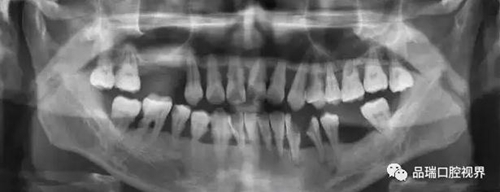

刷牙出血、牙齦紅腫、疼痛,這種情況幾乎人人都有過。在疲勞、生活不規(guī)律,刷牙潦草時(shí)更容易出現(xiàn)。很多朋友以為牙齦出血是因?yàn)槿狈δ撤N維生素。其實(shí),雖然長(zhǎng)期嚴(yán)重缺乏維生素C確實(shí)會(huì)導(dǎo)致牙齦出血紅腫,但除非一連兩三個(gè)月都不吃蔬菜水果牛奶等含有維生素C的食物,否則,除了極少數(shù)人是由于血液病等全身疾病,絕大多數(shù)牙齦出血都是牙齦炎的表現(xiàn)。牙齦出血,原因多為牙齦炎或牙周炎。

牙齦炎 | 牙周炎的前奏

牙周炎是一種漸進(jìn)性的疾病——就是說它并不會(huì)像普通感冒一樣,不管治不治療,只要不繼發(fā)感染,一周左右都會(huì)好。如果不對(duì)炎癥和口腔的刺激因素進(jìn)行控制,牙齦炎會(huì)進(jìn)一步發(fā)展為牙周炎,這就不再是僅限于軟組織的炎癥,而是會(huì)累及牙槽骨,當(dāng)骨質(zhì)緩慢喪失,牙齒就失去了支撐,開始松動(dòng),最終導(dǎo)致牙齒脫落。